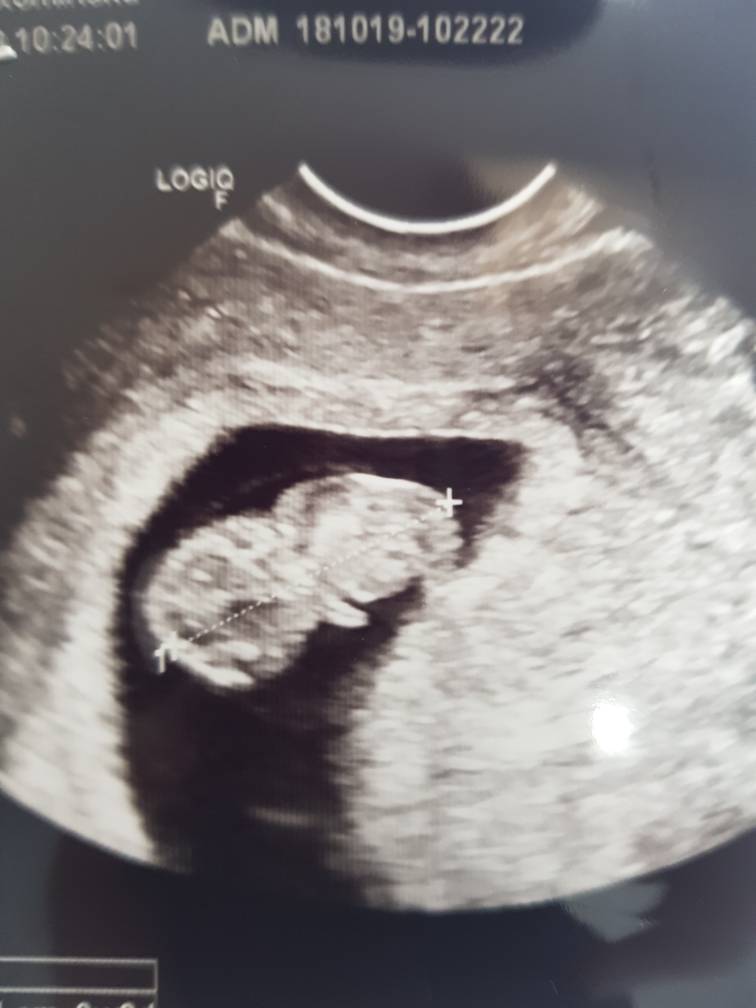

Super ze z dzidzia okejJa już po wizycie. Serduszko pięknie bije. Maluszek ma niecałe 3 cm. 9 tc. Zmieniła się data porodu na 24.5 ale to się okaże [emoji6]

Niestety TSH trochę podwyższone 3.1 więc dostałam leki.Zobacz załącznik 908995